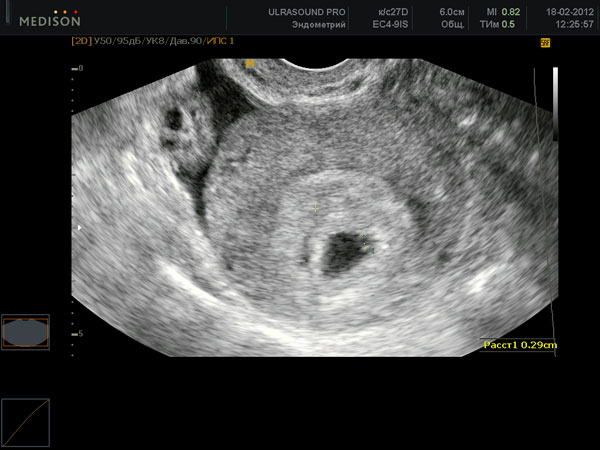

USG

Na początku czwartego tygodnia położniczego badanie raczej nie pomoże. Ale w końcu dobry specjalista zobaczy już coś na sprzęcie wysokiej jakości. Będzie to macica z grubą warstwą endometrium i zarodkiem - małą czarną kropką. Jeśli kobieta miała wcześniej ciążę pozamaciczną, lekarz specjalista na pewno sprawdzi cały system kobiecy.